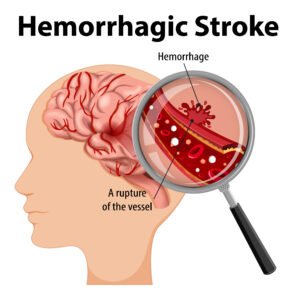

- Stroke